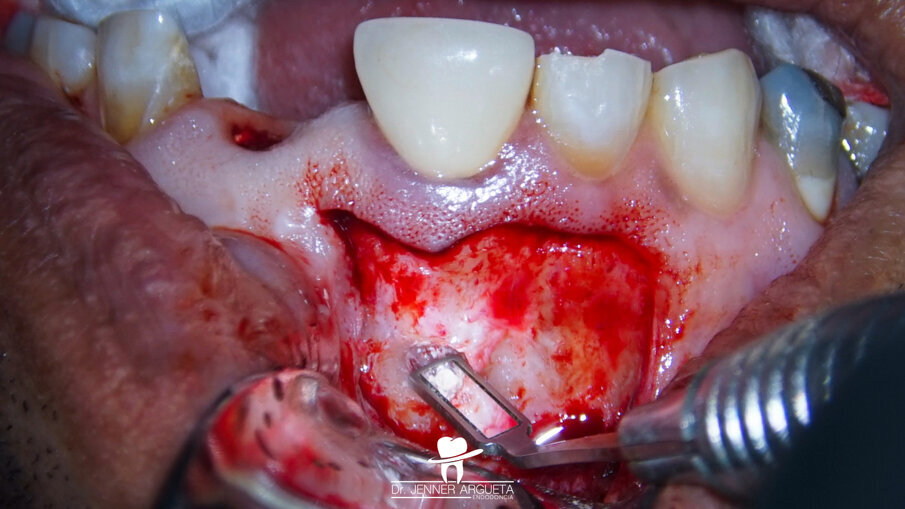

A 50-year-old male patient presented to the dental office with Grade III mobility and intra-oral swelling affecting tooth #21. The patient also reported pain when biting on tooth #11 (Fig. 9). The established diagnosis for tooth #21 was previously treated and acute periapical abscess; cemental tears at mesial and distal root surfaces were detected, as well as a root fracture. The established diagnosis for tooth #11 was previously treated and symptomatic periapical periodontitis.

Tooth #21 was extracted, and a bone grafting material (DM Bone, Meta Biomed) was placed in the area to prepare the site for receiving an implant in the future (Fig. 10). Four weeks after the extraction, periapical surgery was performed on tooth #11, and the minimum amount of root was resected in order to avoid compromising the crown–root ratio. The retro-cavity was prepared using ultrasonic tips (Fig. 11), and CeraPutty was used to retro-obturate the root (Figs. 12 & 13). The sutures were removed five days after surgery (Fig. 14a–c). The four-month follow-up radiograph showed the process of healing in both treated areas (Fig. 15).

Fig. 11: Ultrasonic retro-preparation of tooth #11 during periapical surgery.

Fig. 12: Retro-obturation of tooth #11 during periapical surgery using CeraPutty.

Figs. 14a–c: Post-op suturing sequence. Immediate post-op suturing (a). Five-day follow-up clinical image, just before the suture removal (b). Clinical image immediately post-suture removal, showing good healing of the area (c).